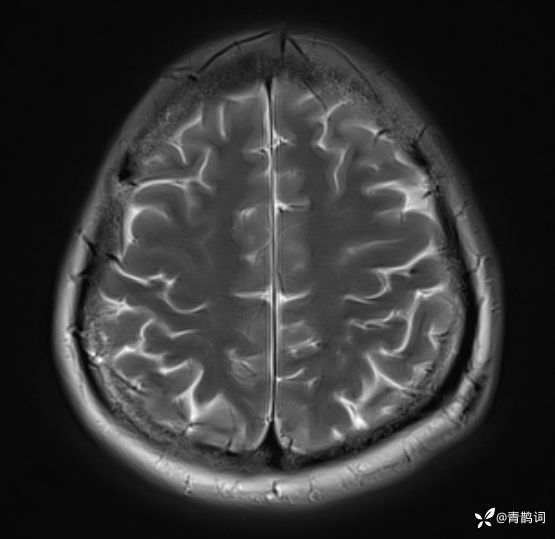

病例分享 | 45岁女患,7年的病史,结合影像学,如何诊断?

1、患者:女, 年龄:45岁

2、主诉:走路不稳渐加重7年,饮水呛咳伴头晕2年渐加重。

3、简要病史:患者于入院前7年出现走路不稳,表现为行走右偏,逐渐加重,易跌倒、不能自理;近2年出现饮水呛咳、吞咽困难及头晕;病程伴有耳鸣、反应迟钝,无恶心、呕吐。既往否认高血压、否认糖尿病、否认冠心病。

4、体格检查:体温36.0℃,脉搏80次/分,呼吸20次/分,血压140/70mmHg。查体:神清,构音障碍;眼球运动自如,双水平性眼震,左视时明显;双侧瞳孔等大同圆,左:右=3mm:3mm,对光反射灵敏;双侧额纹对称,双侧鼻唇沟对称;伸舌居中;四肢肌力4级,肌张力减低,四肢腱反射亢进,双侧Babinski征阳性;粗测感觉未见明显异常;四肢共济运动完成差,左侧为著;脑膜刺激征阴性。

入院后完善磁共振:

FLAIR: